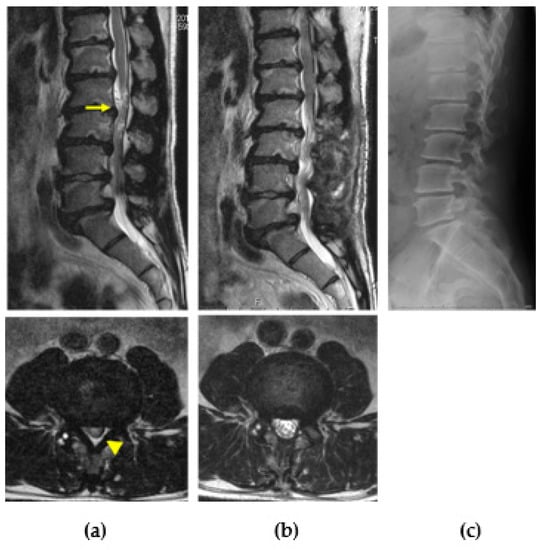

2.1.4. Lumbar Canal Stenosis